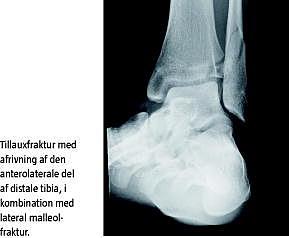

Tillauxfraktur er en ankelfrakturtype, der involverer den anterolaterale del af den distale epifyse i tibia, og det er den fjerdehyppigste frakturtype i ankelområdet hos børn op til 16-års-alderen [1]. Den forekommer hyppigst i aldersgruppen 11-16 år. Lukningen af epifyselinjen i distale tibia starter i den midterste del, efterfulgt af den mediale og til sidst den laterale del [2]. Der er altså en periode, hvor den laterale del af epifysen stadigvæk er åben, mens den mediale er lukket, og dermed er der risiko for fraktur lateralt. Tillauxfraktur opstår ved udadrotation i foden, enten i neutral stilling eller i supination [1]. Derved opstår der et træk i ligamentum tibiofibulare anterius, og da dette ligament hæfter på den laterale del af epifysen, sker der en udrivning af en knogleklods fra den anterolaterale del af distale tibia. Frakturen svarer til epifysefrakturen Salter-Harris type III [3].

Skaden opstod i forbindelse med en sneboldkamp, da patienten gled på iset underlag og forvred det venstre ankelled. Patienten kunne efterfølgende ikke støtte på foden, og der opstod en stor hævelse omkring laterale malleol. Ved palpation var der direkte og indirekte ømhed af laterale malleol samt ti centimeter op langs distale fibula. Der var ingen ømhed eller hævelse ved mediale malleol. Ved hjælp af røntgen påviste man en udislokeret spiralfraktur i den laterale malleol samt et dislokeret ledbærende fragment anterolateralt i distale tibia svarende til en Tillauxfraktur. Da frakturerne var meget tydelige at se på røntgen, blev der ikke foretaget en computertomografi (CT). Patienten blev opereret dagen efter uheldet med anbringelse af osteosyntese i anatomisk stilling. Man fandt Tillauxfrakturen helt løs og displaceret en centimeter fremad. Der blev indsat to lag skruer i laterale malleol samt en spongiosaskrue i Tillauxfragmentet. Patienten blev behandlet med ROM walker i seks uger og måtte kun skyggestøtte de første tre uger. Bruddene helede op uden komplikationer, og patienten opnåede fuldt normal funktion af ankelleddet.

Ved Tillauxfrakturer er det vigtigt med præcis diagnosticering af dislokationsgraden [2]. Der skal altid foretages almindelig røntgen med antero-posterior, lateral og skråprojektion, og ved tvivl om dislokationsgraden skal der gennemføres CT med 3D-rekonstruktioner, som er bedre til at fremstille forskydninger på over to millimeter [4]. Det er vigtigt med CT, da grænsen mellem konservativ og operativ behandling som regel går ved en dislokation på over to millimeter [4]. Hvis frakturen ikke reponeres eksakt, kan der udvikles sekundær artrose med smerter, ledstivhed, varusdeformitet samt mangelfuld lukning af epifysen [2].